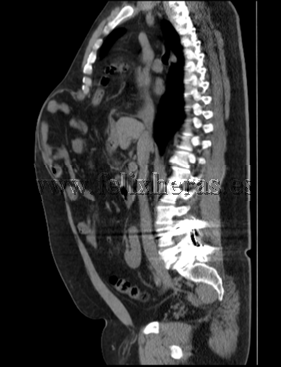

Hernia diafragmática traumática con laparocele gigante